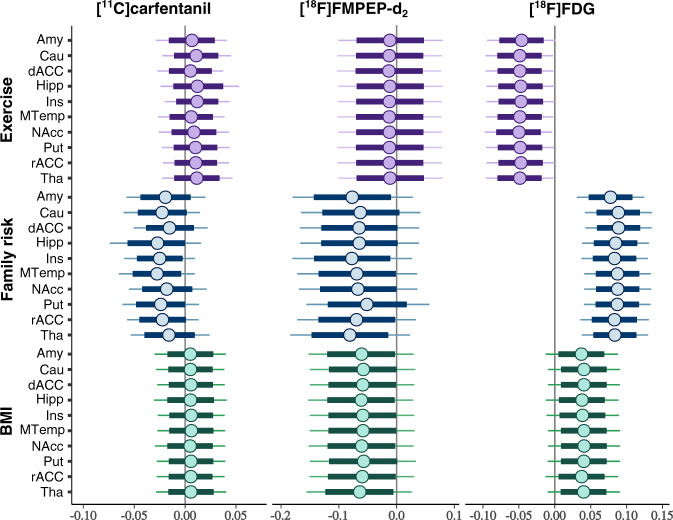

Brain glucose uptake

Increase in Family Risk was associated with globally increased in BGU (Fig. 3, all ROIs in Supplementary Fig. 2). BMI had a moderate positive association with BGU, while increased physical exercise associated with lower BGU (Fig. 3). Full volume visualization of the Family Risk associations is presented in Fig. 4.

μ-opioid receptor availability

Higher Family Risk was associated with lower BPND in frontotemporal cortex, insula and striatum (Figs. 3 and 4, all ROIs in Supplementary Fig. 2), while the effects of BMI and physical exercise markedly overlapped with zero.

CB1 receptor availability

Family Risk and BMI had negative association with VT (Fig. 3, all ROIs in Supplementary Fig. 2). Anandamide (AEA) was the only endocannabinoid to exhibit significant effects to VT. Increase in serum AEA was associated with lower VT in frontal striatum (Supplementary Fig. 3).